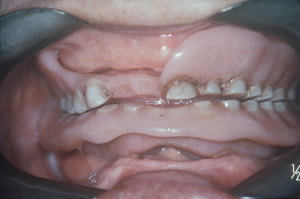

Oral Pathology and Disease Diagnosis Quiz - Quiz

Explore the complexities of diseases affecting the oral and maxillofacial regions. This focused assessment enhances understanding of pathological processes, critical for dental professionals and students aiming to excel in oral health diagnostics.

22. What is EPULIS FISSURATUM?

EPULIS FISSURATUM is a benign tumor-like growth in the mouth often caused by irritation or trauma to the gum tissue. Option A is the correct answer as it accurately describes this condition.